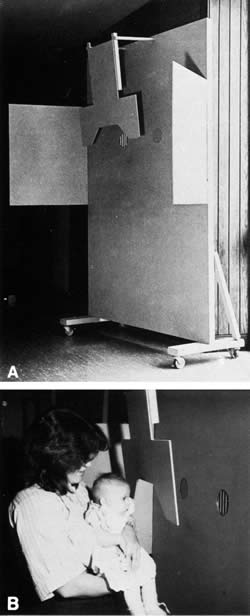

nystagmus. Pediatrics 19:1088, 1957 326. Gorman JJ, Cogan DG, Gellis SS: A device for testing visual acuity in infants. Sight Sav Rev 29:80, 1959 327. Kiff RD, Lepard C: Visual responses of premature infants. Arch Ophthalmol 75:631, 1966 328. Frantz RL, Ordy JM, Udelf MS: Maturation of pattern vision in infants during the first six months. J Comp Physiol Psychol 55:907, 1962 329. Berlyne DE: The influence of the albedo and complexity of stimuli on visual fixation